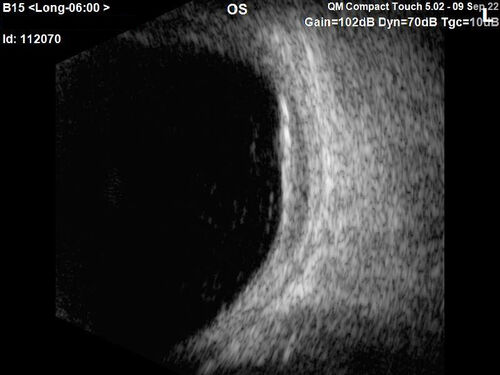

Large chronic choroidal nevus

Autofluorescence image shows guttering at the bottom of the lesion suggesting chronicity. This was documented 23 years prior to these photos